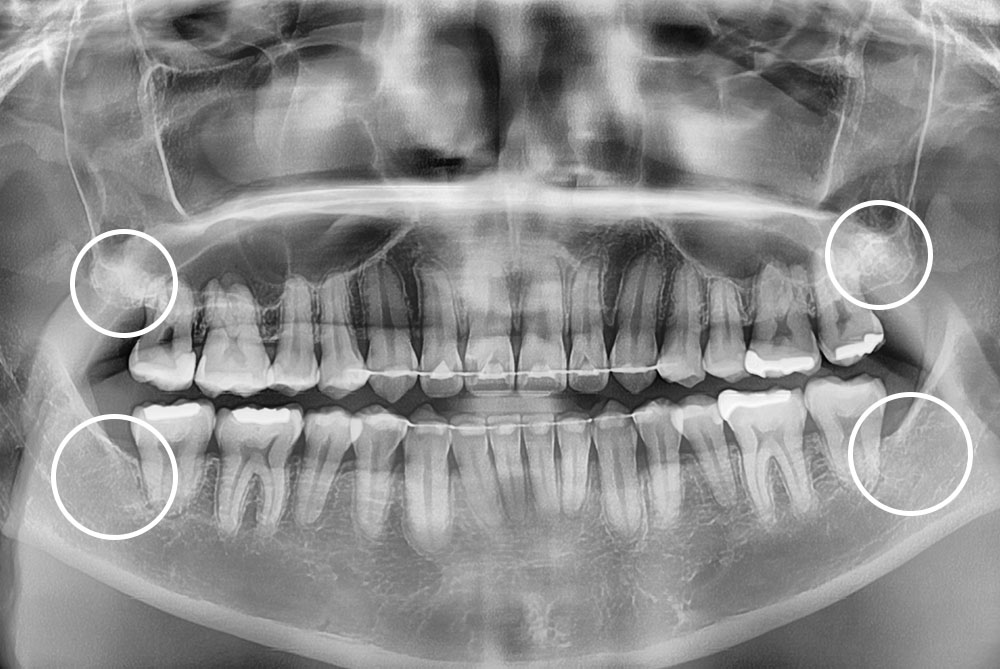

[사랑니] 매복 사랑니 발치

치료후 : 2022-01-17

세종치과는 구강악안면외과학 박사이신 원장님이 발치하는 치과입니다.